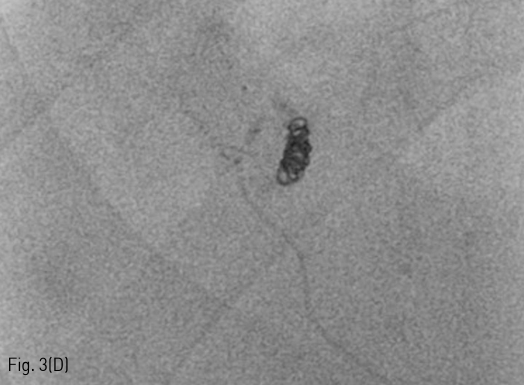

Fig 2C

Follow up liver CT 11 months after RFA. (A-D) There is a connection (arrows) between a branch of the S7 segmental hepatic artery and right posterior portal vein.

Fig 2B